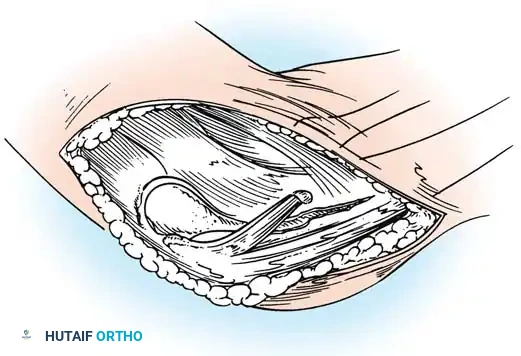

- Approach: Utilize a standard posterolateral (Kocher-Langenbeck) approach to the hip. Incise the fascia lata and split the gluteus maximus in line with its fibers. Identify and carefully protect the sciatic nerve throughout the procedure. Tag and reflect the short external rotators (piriformis, superior gemellus, obturator internus, inferior gemellus) near their femoral insertions to expose the posterior capsule.

Capsulotomy and Joint Preparation

- T-Plasty Incision: Make a transverse incision in the posterior capsule, oriented perpendicular to the acetabular rim, to create a T-plasty. This allows for excellent visualization of the intra-articular space and the posterior labrum.

- Joint Inspection: Evacuate any intra-articular hematoma or loose bodies. Inspect the femoral head for chondral damage and evaluate the posterior labrum. If a soft-tissue defect is identified as the primary cause of instability, a labral repair and capsulorrhaphy are mandatory to recreate a stable joint. A bone block will be used to supplement this soft-tissue reconstruction.

- Capsular Flap Management: Trim the inferior and superior capsular flaps that were created during the T-plasty. Advance the inferior flap superiorly; this maneuver is critical to eliminate the pathological capsular redundancy.

- Superior Flap Imbrication: Imbricate the superior capsular flap over the newly advanced inferior aspect of the capsule. Achieve this by bringing up the most superior suture and tying it through the superior capsular flap in a horizontal mattress fashion, creating a robust, double-layered capsular repair.